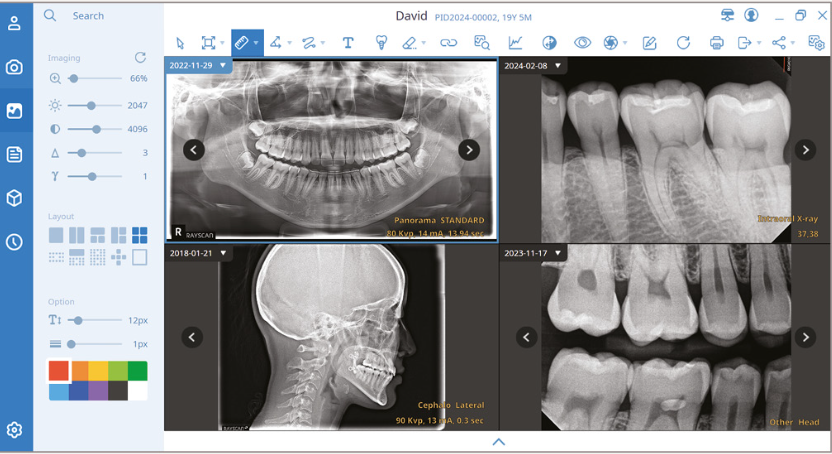

Software

SMARTDent

Software de imégenes 2D

Gestión integral de imágenes dentales

‧ Simulación de implanes & canales nerviosos

‧ Búsqueda simple y poderosa (id, nombre, fecha, modalidad)

‧ Sistema de imágenes completo de 16 bits con DICOM 3.0

‧ Admite dispositivos compatibles con entrada TWAIN

‧ Diseño conveniente